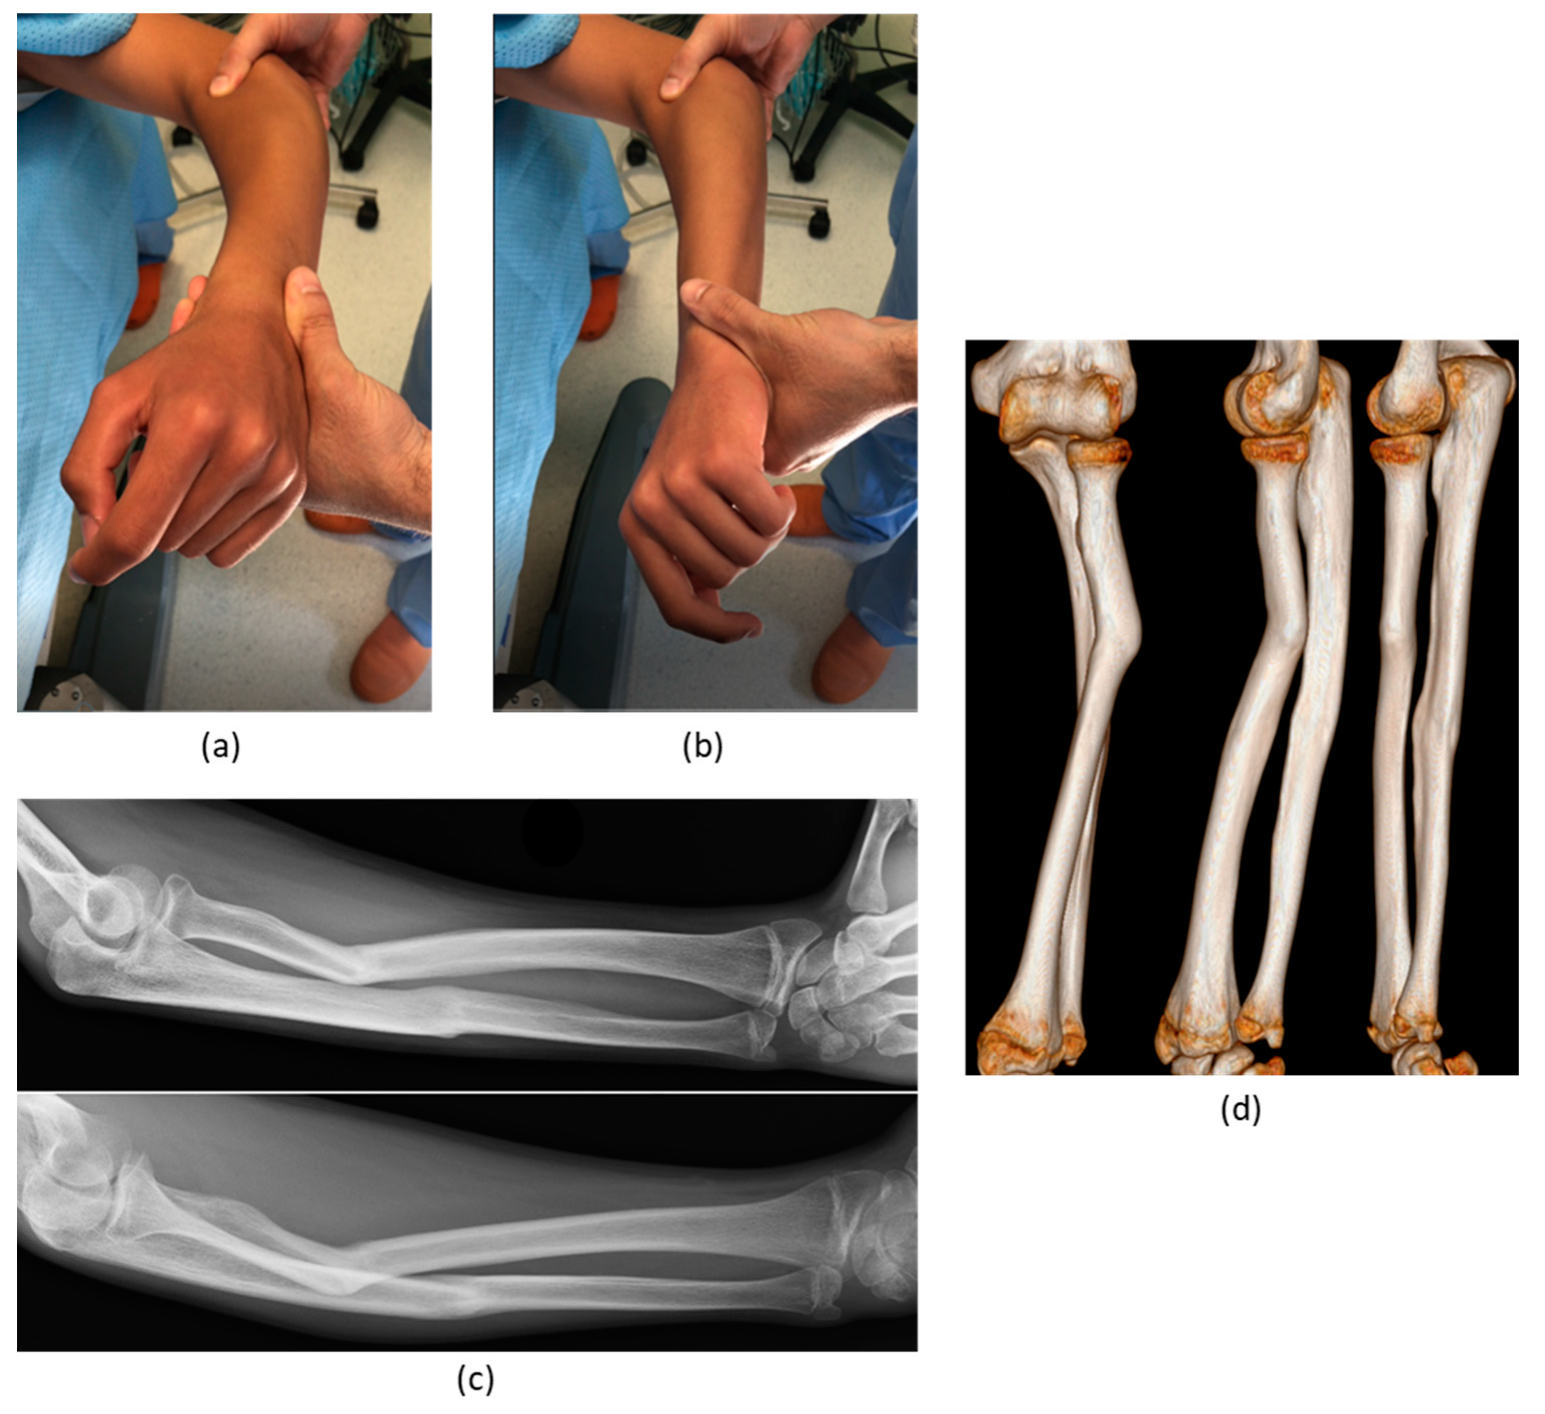

| 2 | M, 13 | Focal fibrocartilagineous dysplasia | Congenital | Bifocal osteotomy stabilized with external fixator | Heterotopic bone formations | Fair (residual dislocation of the radial head with shortening of the ulna) |